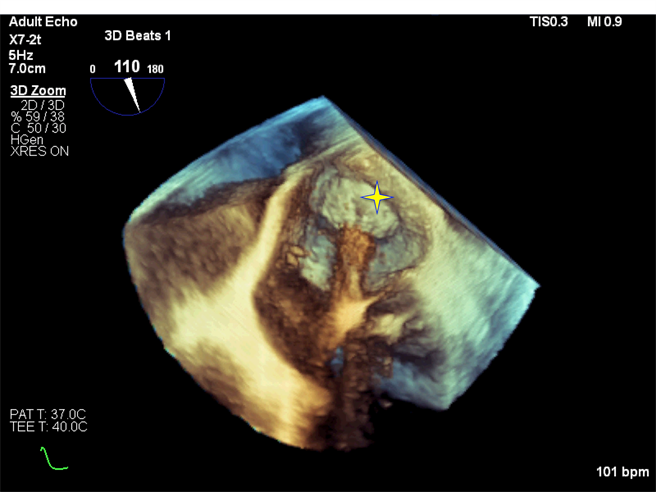

新竹台大分院心臟科主任廖敏村说明,过去临床上做心房颤动的术式,都是利用超音波来协助电烧手术中心房中膈穿刺的步骤而已。冷冻导管消融术中,常会使用显影剂注射来评估肺静脉回流至左心房的血流是否被冷冻消融术的气球封堵密合。近年来随着高阶超音波机器影像画质的提升,肺静脉回流是否已被气球封堵密合,已经能透过彩色超音波的血流讯号有效评估,不需使用显影剂,可以降低对显影剂过敏、有慢性肾病变病人的手术风险。